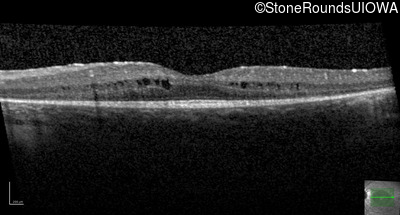

Age at visit: 9 years